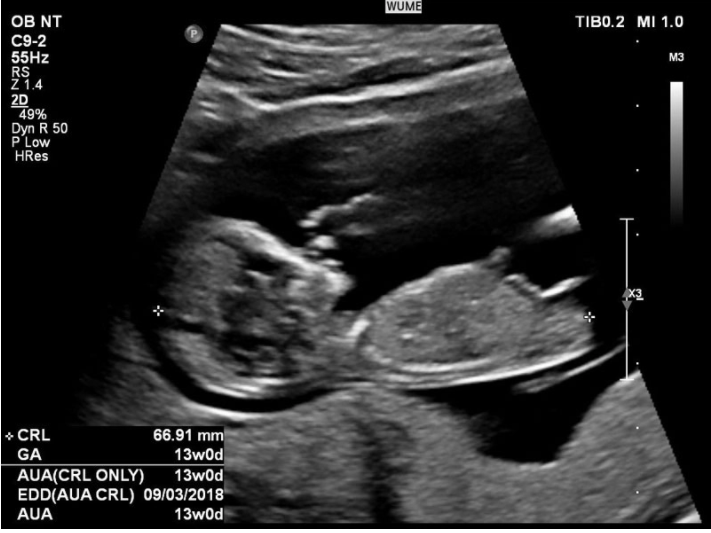

胎儿生长指数有很多术语。下面介绍几个胎儿重要指标的名词和缩写,供孕妇参考:

- GA:从末次月经第一天算起的胎龄。

- CRL:头对接长度。

- BPD:双顶径,即水平跨过颞骨测量的最大直径。

- FL:股骨的长度。

- EFW:估计胎儿的体重。

- TTD:横跨腹部测量的直径。

- APTD:在胎儿腹部前后测量的直径。

- HC:胎儿头部的周长。

- AC:腹部的周长。

- AF:羊水。

- AFI:羊水指数。

- OFD:枕骨的直径,测量从婴儿前额到头骨后部的最大部分。

- EDD:预计出生日期。